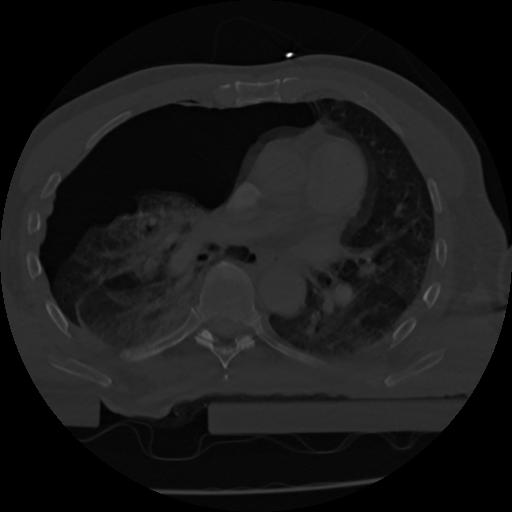

22 ANGIO,CE,Vol,0.5,ANGIO,,